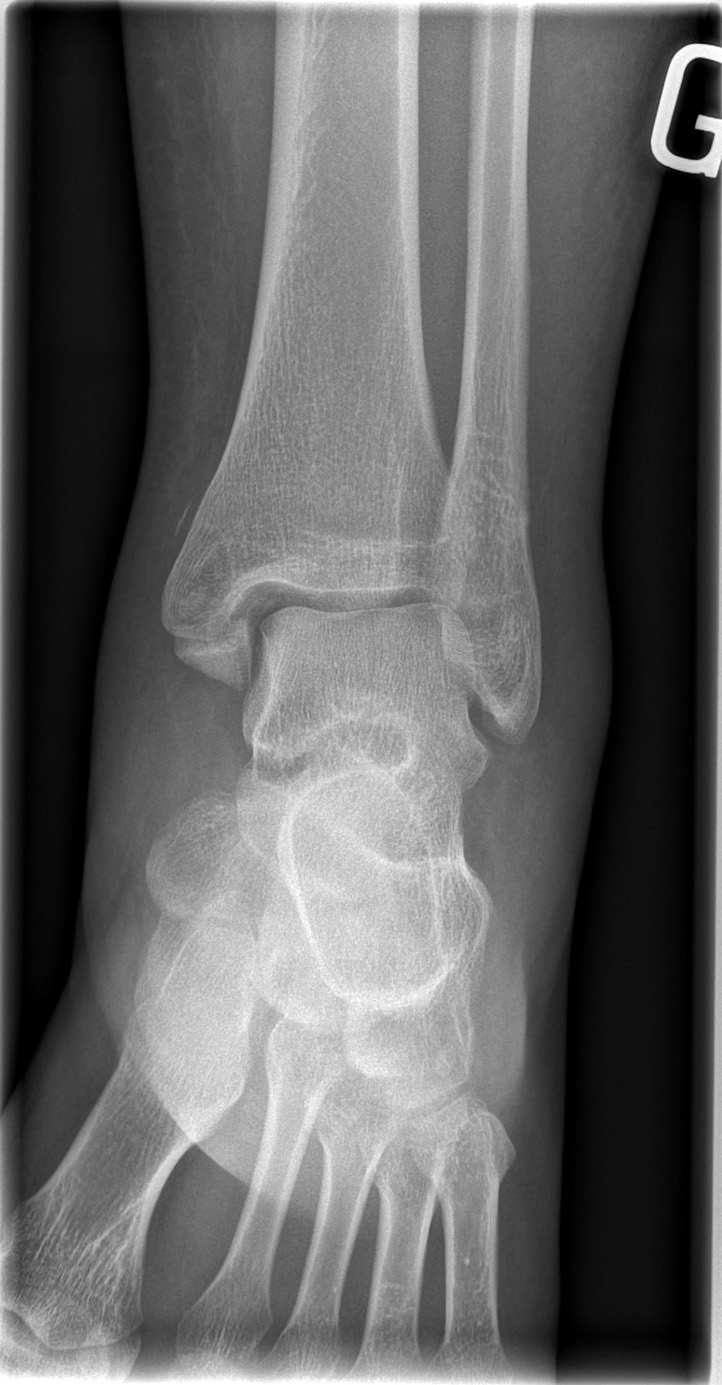

26-year-old male:

Ankle eversion trauma while playing soccer.

Bimalleolar fracture

Lateral malleolus oblique fracture (Weber B) concomitant to a medial malleolus transverse fracture.

Symmetrical mortise

The mortise appears symmetrical on the mortise view.

Mortise (15° internal rotation)

• Mortise (15° internal rotation)